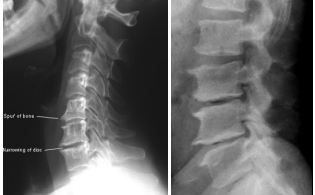

Lesão degenerativa discal

causa…

• Causa:

1. Redução do espaço discal

2. Esclerose óssea do platô vertebral (CV fica mais

branco)

3. Osteófitos marginais (bico de papagaio)

4. Fenômeno do vácuo discal: pois um dos produtos

de degeneração do disco vertebral é nitrogênio

aonde estão as lesões nas imagens?

1. Lesão degenerativa discal de C5-C6- C7

2. Lesão degenerativa discal de L2-L3-L4-L5